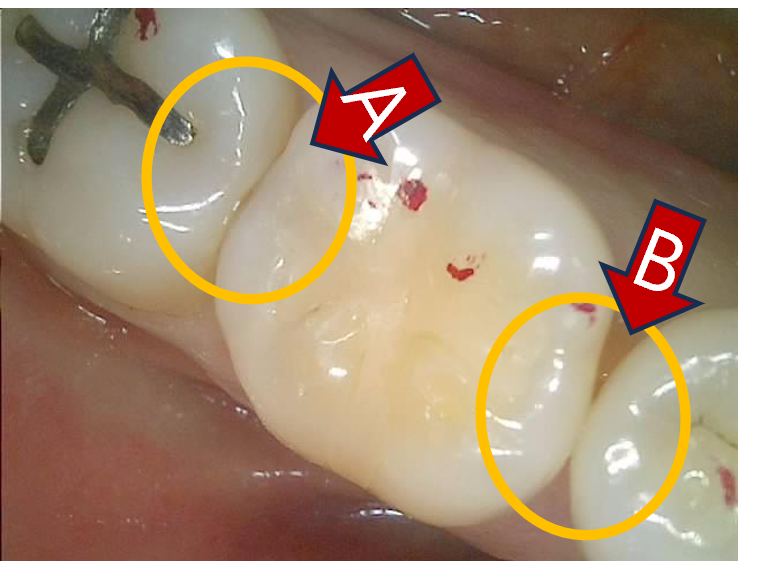

이제 #36을 체크. 보인다, 인접면 충치.

인접면 충치 치료 중, 옆치아의 맞닿은 면의 충치 발견

교합면의 변연융선(marginal ridge)을 보존해주면서 조심조심 충치를 제거.

아직 조금 남았다.

인접면 충치 치료를 위해 교합면을 보존하면서 충치만 제거

이제 깔끔하게 제거됨.

인접면 충치 치료 중, 옆치아의 맞닿은 면 충치 제거 완료